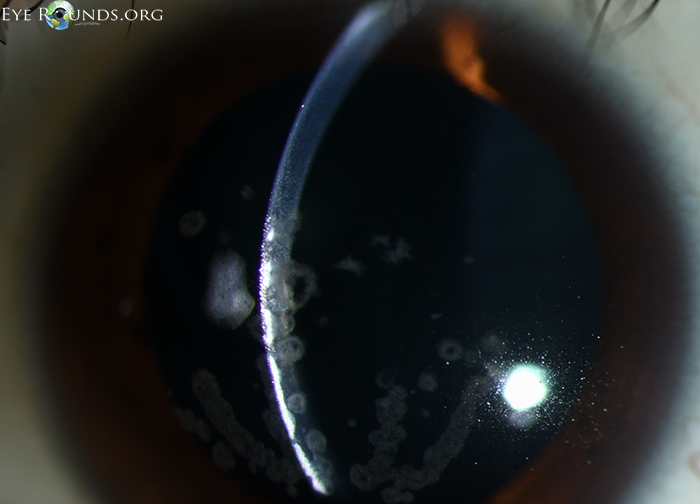

각막의 기질에 빵부스러기, breadcrumb 모양의 흰색의 침착물이 쌓이는데,

이는 각막의 중심부, 기질의 앞쪽쯕에 모이게됩니다.

혼탁의 모양은 둥글며, 병변들의 윤곽이 명확하며

흔히 눈송이, 빵부스러기 등의 모양으로 하고 있으며, 경계가 명확하여,

병변이 없는 부위과 구분됩니다.

병변이 진행하면서, 중심부의 혼탁이 융합되어 커지거나, 주변부로 확장될수 있으며,

드물게 병변의 깊이도 깊어져 기질의 뒤쪽으로도 확장되는 경우도 있습니다.